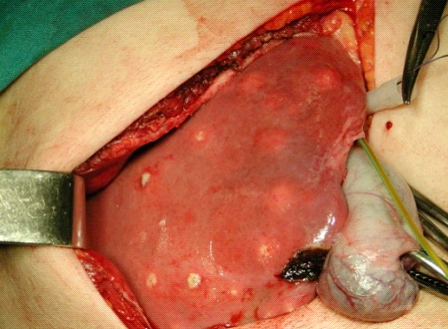

Cirúrgico

A drenagem cirúrgica aberta foi realizada amplamente nos anos 70, sendo indicada como tratamento de escolha até o início dos anos 80. Em geral, é reservada para aqueles pacientes nos quais a drenagem ou aspiração percutânea não obtiveram sucesso, pacientes sépticos, quando ocorre ruptura da lesão ou quando é necessária cirurgia para tratamento da doença de base. A experiência de Herman e colaboradores, do Departamento de Gastroenterologia da FMUSP, de 1975 a 1993 (31 casos) é de bons resultados em 91,5%.